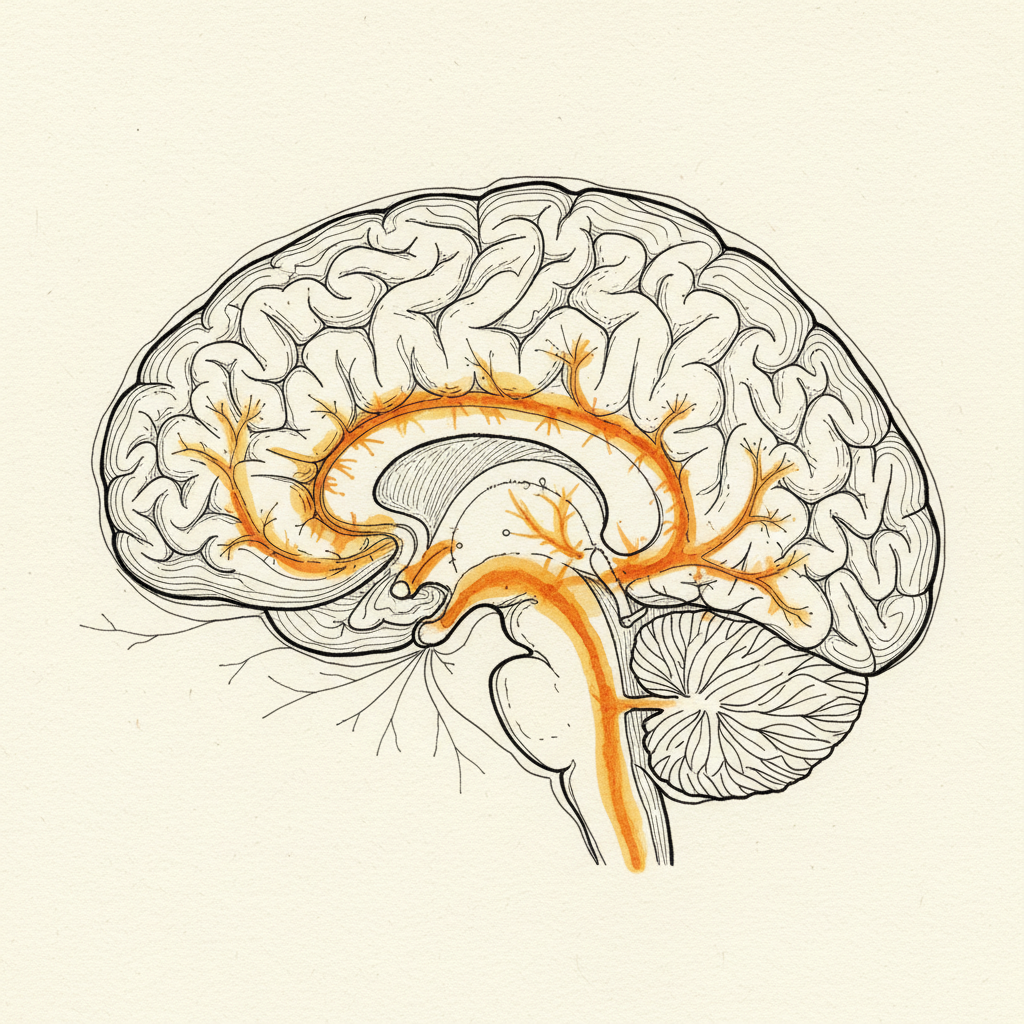

First, the brain reorganized its map of the painful area. Flor’s research showed that chronic back pain physically changes the brain’s representation of the affected region [9]. The cortical map blurs. The brain’s ability to precisely locate and control that area degrades. It is like a GPS losing resolution on one neighborhood. The commands it sends to that region become coarser. Less precise. More likely to generate compensatory movement that loads the area differently and perpetuates the cycle.

Second, the brain reorganized its motor strategy. Hodges and Moseley documented that pain changes how the brain activates muscles in the region [8]. Anticipatory postural adjustments shift. The deep stabilizers stop firing on time. The superficial muscles take over the stabilization job they were never designed to do. This reorganization persists long after the tissue heals. The brain is not responding to current damage. It is running the motor strategy it built during the injury.

Chronic pain is increasingly understood as a nervous system phenomenon rather than a tissue damage problem. Research by Flor et al. (1997) demonstrated that chronic back pain physically reorganizes the brain’s representation of the affected region. The cortical map blurs, reducing the brain’s ability to precisely control that area. Hodges and Moseley (2003) showed that the brain restructures its motor strategy under pain, changing anticipatory postural adjustments in ways that persist beyond tissue healing. The body schema (Paillard 1999), the brain’s internal model that generates both posture and pain predictions, enters a protective state (Porges 2011). The system organizes around perceived threat rather than efficient movement. This protective state generates the muscle bracing, movement avoidance, and compensatory loading patterns that perpetuate the pain cycle. The pain is real. The generator is in the nervous system’s threat model, not in ongoing tissue damage.

The brain’s map of the painful region must be restored. The cortical blurring that Flor documented [9] degrades the brain’s ability to precisely control the painful area. Two-point discrimination research by Moseley shows that restoring the map’s resolution is both possible and therapeutic. When the brain can locate the region with precision, its motor commands to that region become precise. Compensation decreases. The pain-generating loading pattern begins to change.